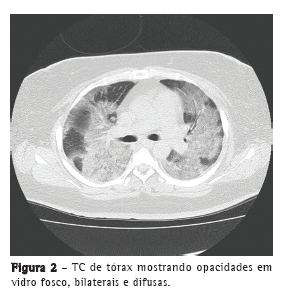

We report a successfully treated case of PIV3 pneumonia mimicking influenza pneumonia in a 31-year-old female patient with asthma. The patient had high fever (39.5°C), general fatigue, systemic joint pain, and anorexia for two days before being referred to our medical center. She was a current smoker and had a history of smoking (20 pack-years) and of bronchial asthma (no current use of medication). The patient also had poorly controlled diabetes mellitus and a body mass index of 30 kg/m2. A chest X-ray revealed diffuse ground-glass opacities in both lungs (Figure 1). Laboratory tests showed severe inflammatory reaction (C-reactive protein = 19.2 mg/dL and ESR = 83 mm/h). She had severe respiratory failure and an SpO2 of 80% on room air at the first visit, and oxygen therapy was started with noninvasive positive pressure ventilation. Because of the severe respiratory failure, bronchoalveolar lavage was not performed. Although the result of a rapid influenza antigen detection test was negative, she was diagnosed with influenza pneumonia on the basis of influenza-like symptoms and radiological findings, such as diffuse ground-glass opacities (Figure 2).